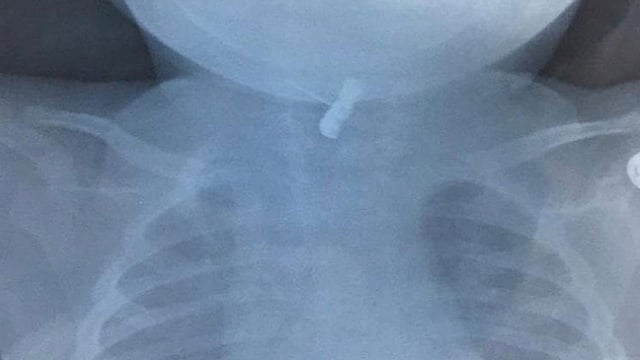

وأوضحت صحة حفر الباطن أنه بعد إجراء الفحوصات والأشعة اللازمة تبين وجود دبوس بالحلق، وعلى الفور باشر الفريق الطبي بإجراء عملية جراحية ناجحة، تم من خلالها استخراج الدبوس بواسطة منظار عن طريق الفم.